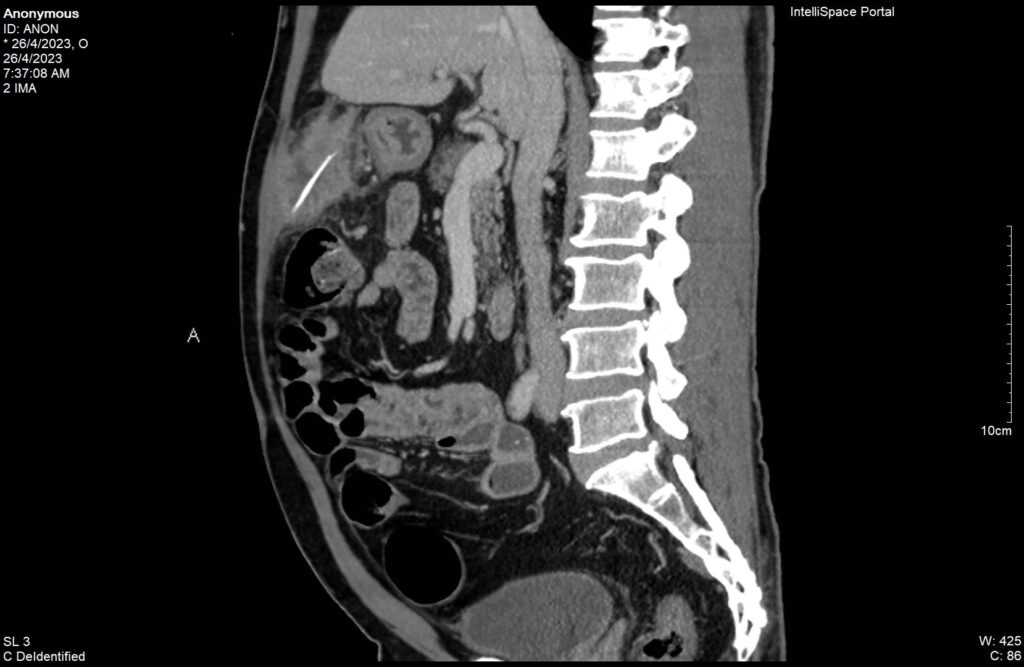

Dù đã tự uống thuốc giảm đau nhưng không thuyên giảm, cơn đau càng ngày càng tăng nên nhập viện cấp cứu. ThS. BS Phạm Hoàng Thiên- Trưởng Khoa Cấp cứu, BV Hoàn Mỹ Sài Gòn người trực tiếp tiếp nhận bệnh cho biết “Qua thăm khám ban đầu tại khoa Cấp cứu, nghi ngờ có khối áp xe ổ bụng trên người bệnh có các bệnh mạn tính nặng như tăng huyết áp, bệnh tim thiếu máu cục bộ, đái tháo đường, suy thượng thận và viêm dạ dày, chúng tôi tiến hành cho người bệnh chụp CT bụng và vùng chậu bằng thuốc cản quang. Kết quả cho thấy người bệnh bị áp xe ổ bụng vùng trước hang môn vị dạ dày do có dị vật dạng que thẳng dài 40mm, đường kính ngang 2mm nghi đâm xuyên thành dạ dày ra ngoài”

Phim CT ghi nhận dị vật trong đường tiêu hóa